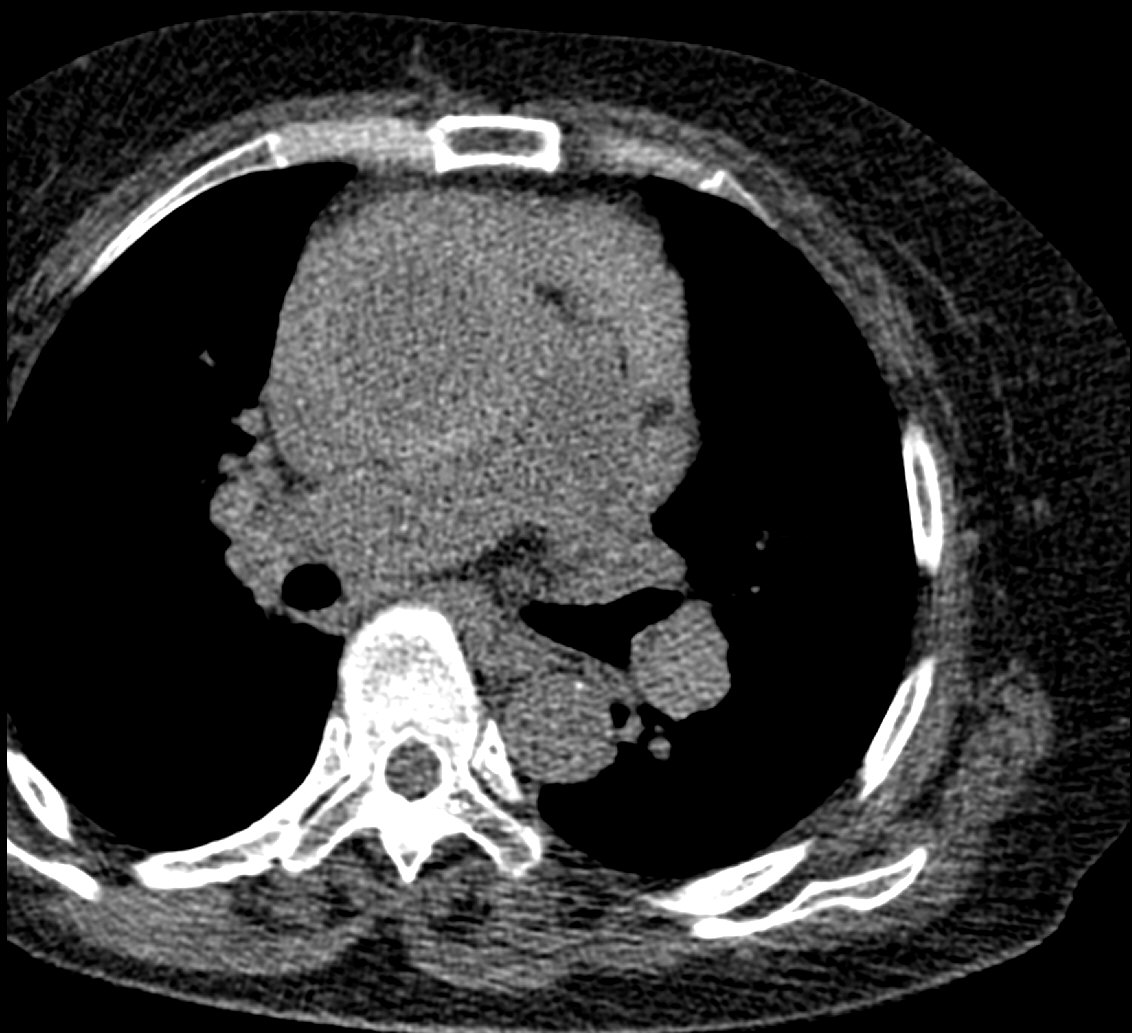

F/73, Incidentally found right atrial mass on echocardiography for evaluation of orthopedic surgery. Previous pulmonary tuberculosis (+), DM (-), HTN (-)

Hwanseok Yong, Korea University Guro Hospital